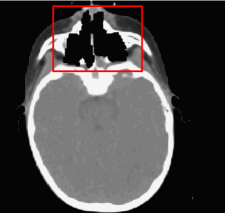

The strategy followed in the nominal treatment (PLAN-NOM) was to draw safety volumes around the metallic rods and to apply hard dose constraint to such volumes of interest (VOIs), as shown in Fig.2, such that the pencil beams of the four fields (F1, F2, F3, F4) involved in the treatment were safe from hitting the rods.

Figure 2: Patient with metallic cage: nominal IMPT dose distribution; inside the patient volume, the green contour corresponds to the PTV and the red ones to the OARs; otuside the patient volume, the safety VOIs and the effective countours of the 4 metallic rods are visible; the fields F1, F2, F3, F4 used for PLAN-NOM and PLAN-OL-1 are also shown.